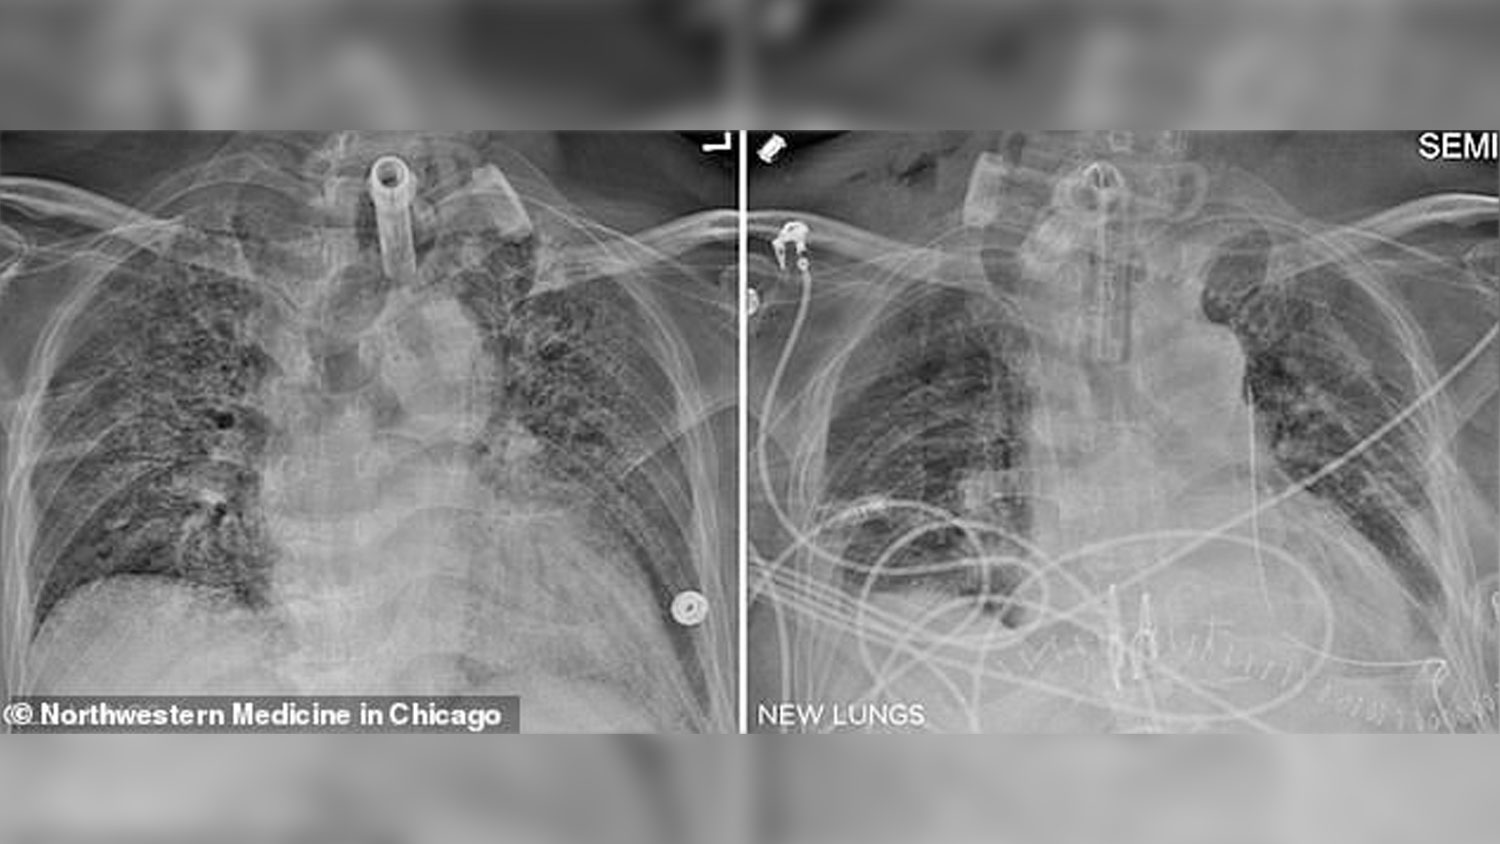

«Красивые, здоровые»: пациент получил легкие от донора, перенесшего COVID-19

Прошла первая пересадка легких от человека, переболевшего коронавирусом

В США врачи впервые пересадили легкие от донора, который переболел COVID-19, а затем умер по не связанной с болезнью причине. Пациентом стал мужчина, чьи легкие отказали из-за коронавируса. По словам врачей, сейчас пациент в норме и постепенно восстанавливается.

Американские врачи из клиники Северо-Западного университета впервые пересадили пациенту с COVID-19 легкие от донора, уже перенесшего болезнь. Об этом сообщает издание Daily Mail.

Донор переболел COVID-19 в 2020 году, успешно вылечился, но затем скончался по несвязанной с болезнью причине. Пациент, 60-летний медработник из Иллинойса, заразился коронавирусом еще в мае 2020 года. Он переносил инфекцию настолько плохо, что ему понадобилась экстракорпоральная мембранная оксигенация, при которой аппарат перекачивает и насыщает кислородом кровь пациента вне тела, снимая эту функцию с сердца и легких.

В феврале 2021 года мужчину перевели в клинику Северо-Западного университета, где он попал в список пациентов, которым необходима пересадка легких. При COVID-19 операция сложнее обычной пересадки из-за повреждений, нанесенных вирусом. Кроме того, врачам необходимо дождаться, пока организм избавится от вируса, и при этом следить за тем, чтобы органы пациента не отказали.

Донора удалось подобрать в течение недели: этот человек ранее перенес COVID-19, хотя и в умеренной форме. Но вирус не повредил легкие, и они подходили для трансплантации. Существовали определенные риски — в организме донора мог сохраниться вирус, и пересадка бы погубила пациента. Чтобы удостовериться, что в организме донора не осталось SARS-CoV-2, врачи провели биопсию легких, а также изучили скапливающуюся в них жидкость. Тесты оказались отрицательными.

По словам врачей, пересадка прошла успешно.

«Наш пациент получил красивые, здоровые легкие и продолжает восстанавливаться в оптимальном темпе», — говорит Бхарат.